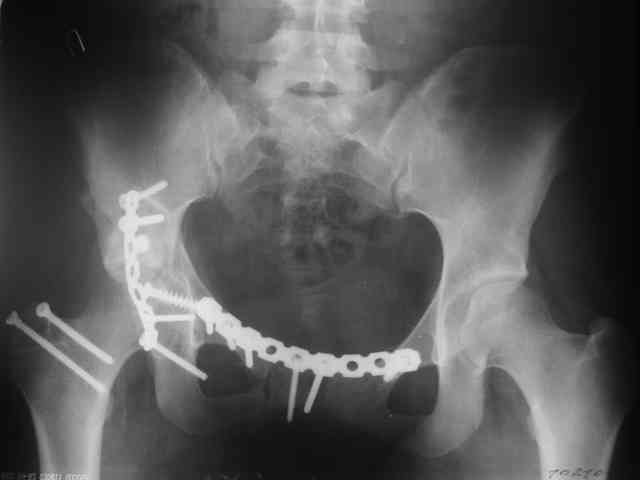

Трудности возникли сразу после рассечения большой ягодичной мыцы - короткие наружные ротаторы едва ли определялись - головка и шейка (как видно на

снимке) ушли в таз, пришлось воспользоваться дистрактором( ручные попытки выдернуть голову из под проксимального фрагмента - безуспешны) Шарнирный дистрактор - великое изобретение, без него репозиция была просто невозможна.

Дальше как обычно: рекон пластнина на заднюю колонну. Устранить смещение передней колонны из заднего доступа оказалось невозможным, пришлось

перевернуть больную на спину и из подвздошного доступа вернуть переднюю колонну на место. Другая проблема возникла с фиксацией лонной кости,

пришлось открывать ся над лобком и ретроградно двумя винтами фиксировать обе ветви лобковой кости справа и слева.

P.S. в приложении R пациентки с похожей проблемой доступа.. за исключением того, что перелом

двухколонный. Вертлугу лечили Y доступом.